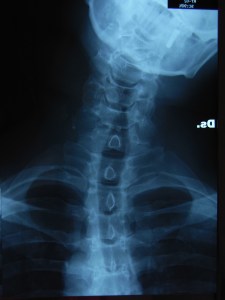

* le foto delle radiografie di Antonio in flessione laterale destra e sinistra.